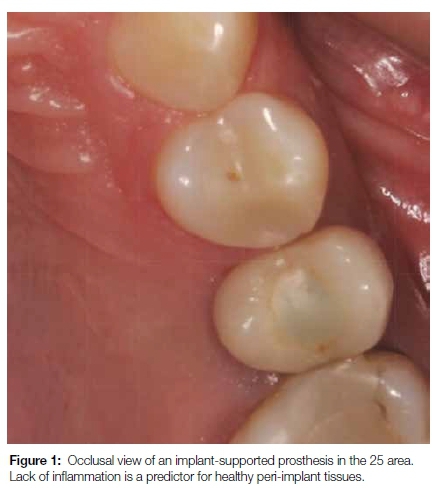

Diminished inflammatory signs (redness, heat, pain, swelling and loss of function) in peri-implant disease (Figure 1) bring into question the clinical parameters proposed by several consensus groups. We know that distinct anatomical differences exist between the tissues surrounding teeth and dental implants. Peri-implant connective tissue resembles scar-like tissue as it contains a high number of collagen fibers and low numbers of fibroblasts and vascular structures. The resulting decrease in blood supply, and a lack of the vascular plexus in the peri-implant tissues, make the tissues more susceptible to bacterial insult, while also showing fewer signs of inflammation.20,21